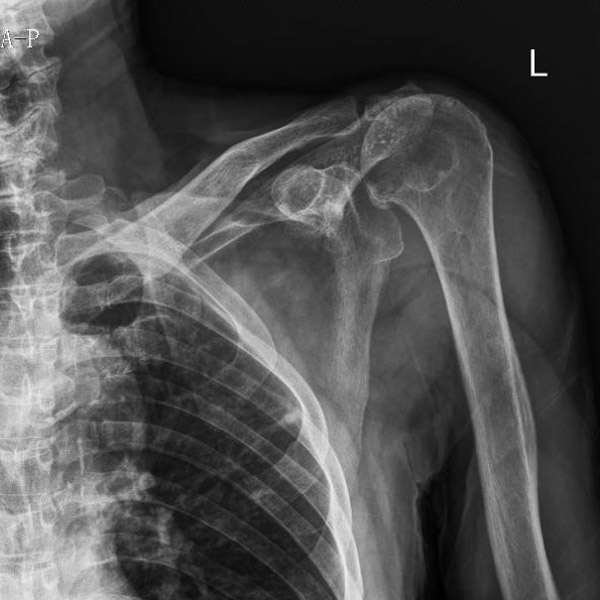

▲術前術后對比

江爺爺因車禍導致左肩疼痛伴活動受限,遂在家人陪同下到柳州市人民醫院創傷骨科就診,經CT檢查后,發現患者左肩袖損傷、左側肩峰骨折、左肩關節脫位,傷情非常嚴重。

“這種情況保守治療的效果不會太好,為最大程度恢復肩關節功能,就需要為患者進行左側反向全肩關節置換手術。”創傷骨科副主任舒文介紹,反向全肩關節置換手術是將組成整個肩關節的肱骨頭、肩胛骨關節盂全部換成人工的,并將肱骨頭與肩胛骨關節盂位置對調——假體的“肱骨頭在上、肩胛骨關節盂在下”,和人體真正的肩關節方向相反。這是近年國際上用來治療巨大不可修復肩袖損傷等復雜肩關節疾病的最新、有效技術。